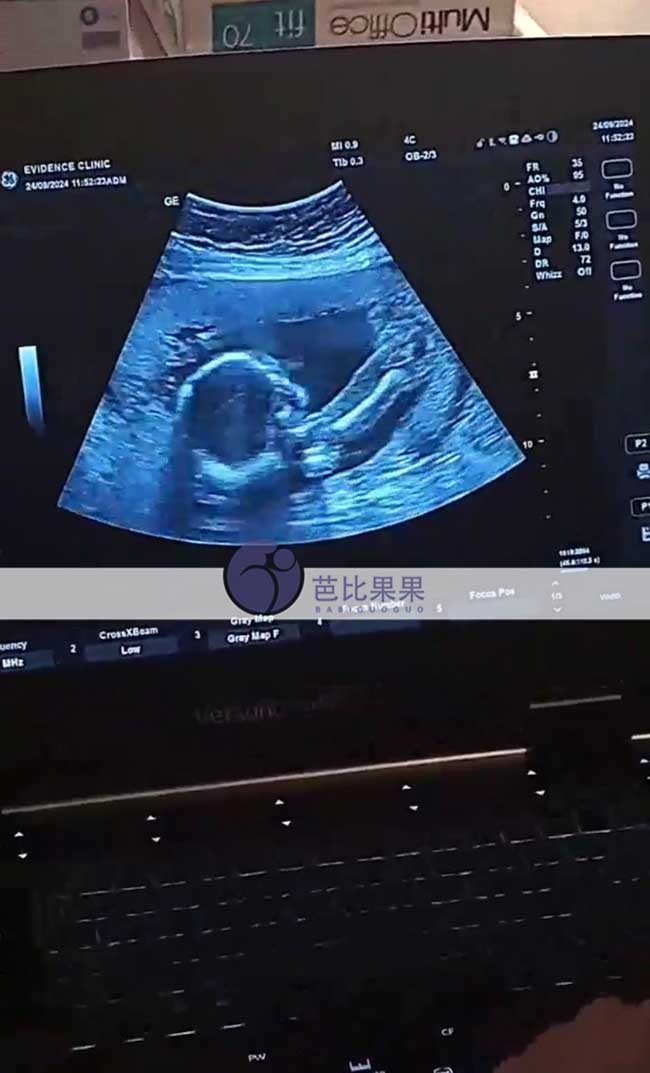

单身L先生到格鲁吉亚助孕匹配的试管妈妈做孕20周B超

单身L先生到格鲁吉亚助孕匹配的亚美尼亚试管妈妈来医院做孕20周B超,胎宝宝发育健康